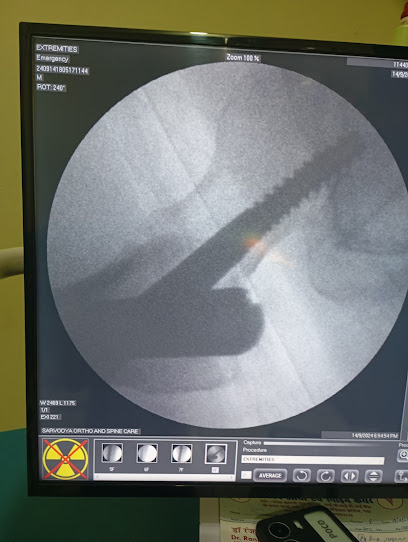

About Dr Ranjay kumar

At our clinic in Gaya, your health is our top concern. With specialization in advanced medical care, we provide expert consultations and personalized treatments designed for your family’s well-being. Visit us today and experience dedicated healthcare services in Gaya.